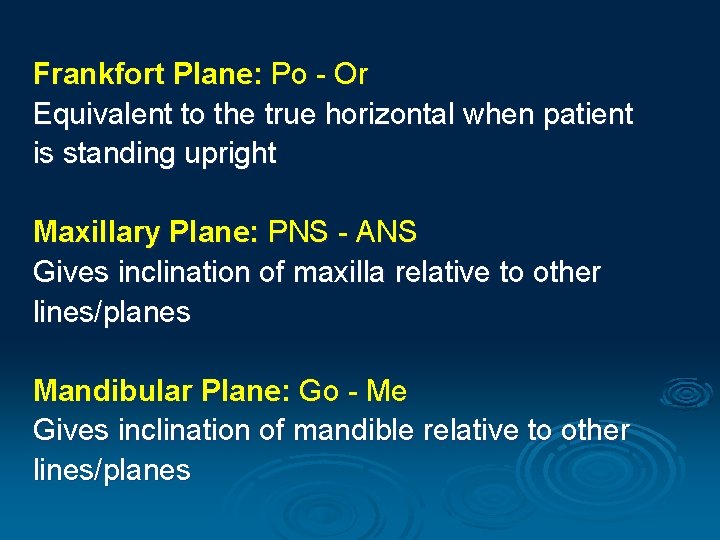

Frankfort Plane: Po - Or Equivalent to the true horizontal when patient is standing upright Maxillary Plane: PNS - ANS Gives inclination of maxilla relative to other lines/planes Mandibular Plane: Go - Me Gives inclination of mandible relative to other lines/planes